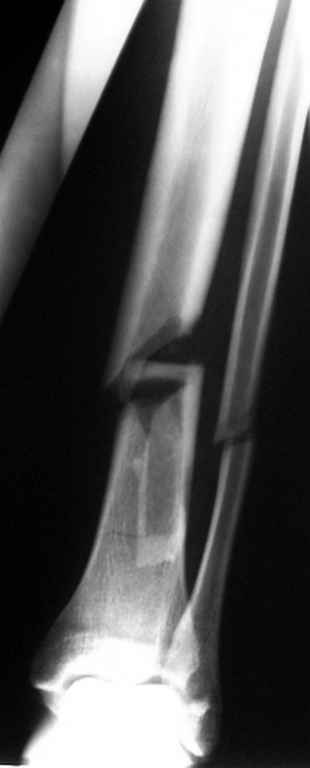

На голени что-то сделать с отломком вынуждает угроза перфорация кожи, перекрытие отломком входа в канал. Не всегда надо делать разрез, можно и шилом чрескожно фрагмент сдвинуть. Наверно, еще и повреждение сосудистого пучка, когда "виновник" прямо поперек перерезанной артерии и лежит - такое не каждый за всю свою профессиональную жизнь

встретит.

То есть в представленных ситуациях при штифтовании ни на бедре, ни на голени не нужно делать ни открытую, ни закрытую (с помощью шильев,

спиц, еще каких-то "джойстиков") репозицию. Все, что нужно - восстановить ось, длину и ротацию.

Перелом большеберцовой кости почти околосуставный, могут потребоваться дополнительные меры для восстановления оси (отклоняющие спицы или винты), и запирающих винтов в дистальный отломок желательно побольше. Задний край не сломан ли там, не разобрал по этим снимкам.

>Сами собираемся оперировать голень и думаем, что без "открытия" места перелома не обойтись.

"Открытие" "открытию" рознь. Мне видится такая последовательность действий: попытаться установить проводник закрыто на вытяжении или дистракторе. Если прошел -рассверлиться, если нет поправить направление проводника через разрез такой величины, чтобы можно это было сделать но не более того.Если осколок, стремящийся в канал свободен от мягких тканей - удалить его. Удаляли вываливающиеся отломки "перстневидной" формы по более представленного, тем не менее сращение наступало. Если удастся все провести закрыто, манипуляции с отломком нужны, если он будет стремиться перфорировать кожу.Бывает, что для этого не обязательно открываться, просто подтолкнуть осколок через кожу или (цитата:))шилом.

Общее MHO по поводу осколков:

1.мелкие не стоят внимания, если не давят на сосудисто-нервный пучок, угрожают перфорацией и т.п., и т.д.,

2.крупные, если создают дефект в области перелома, должны находиться как можно ближе к области перелома, как депо материала для костеобразования, отнюдь не должны быть точно репонированы.